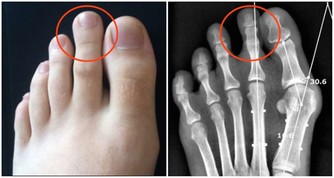

8. 你已經被診斷患有炎性疾病

狼瘡和類風濕性關節炎有兩個可怕的共同點:更可能影響女性,都會增加心髒病的風險。這一切都歸結於炎症,炎症損害血管,導致斑塊積聚。